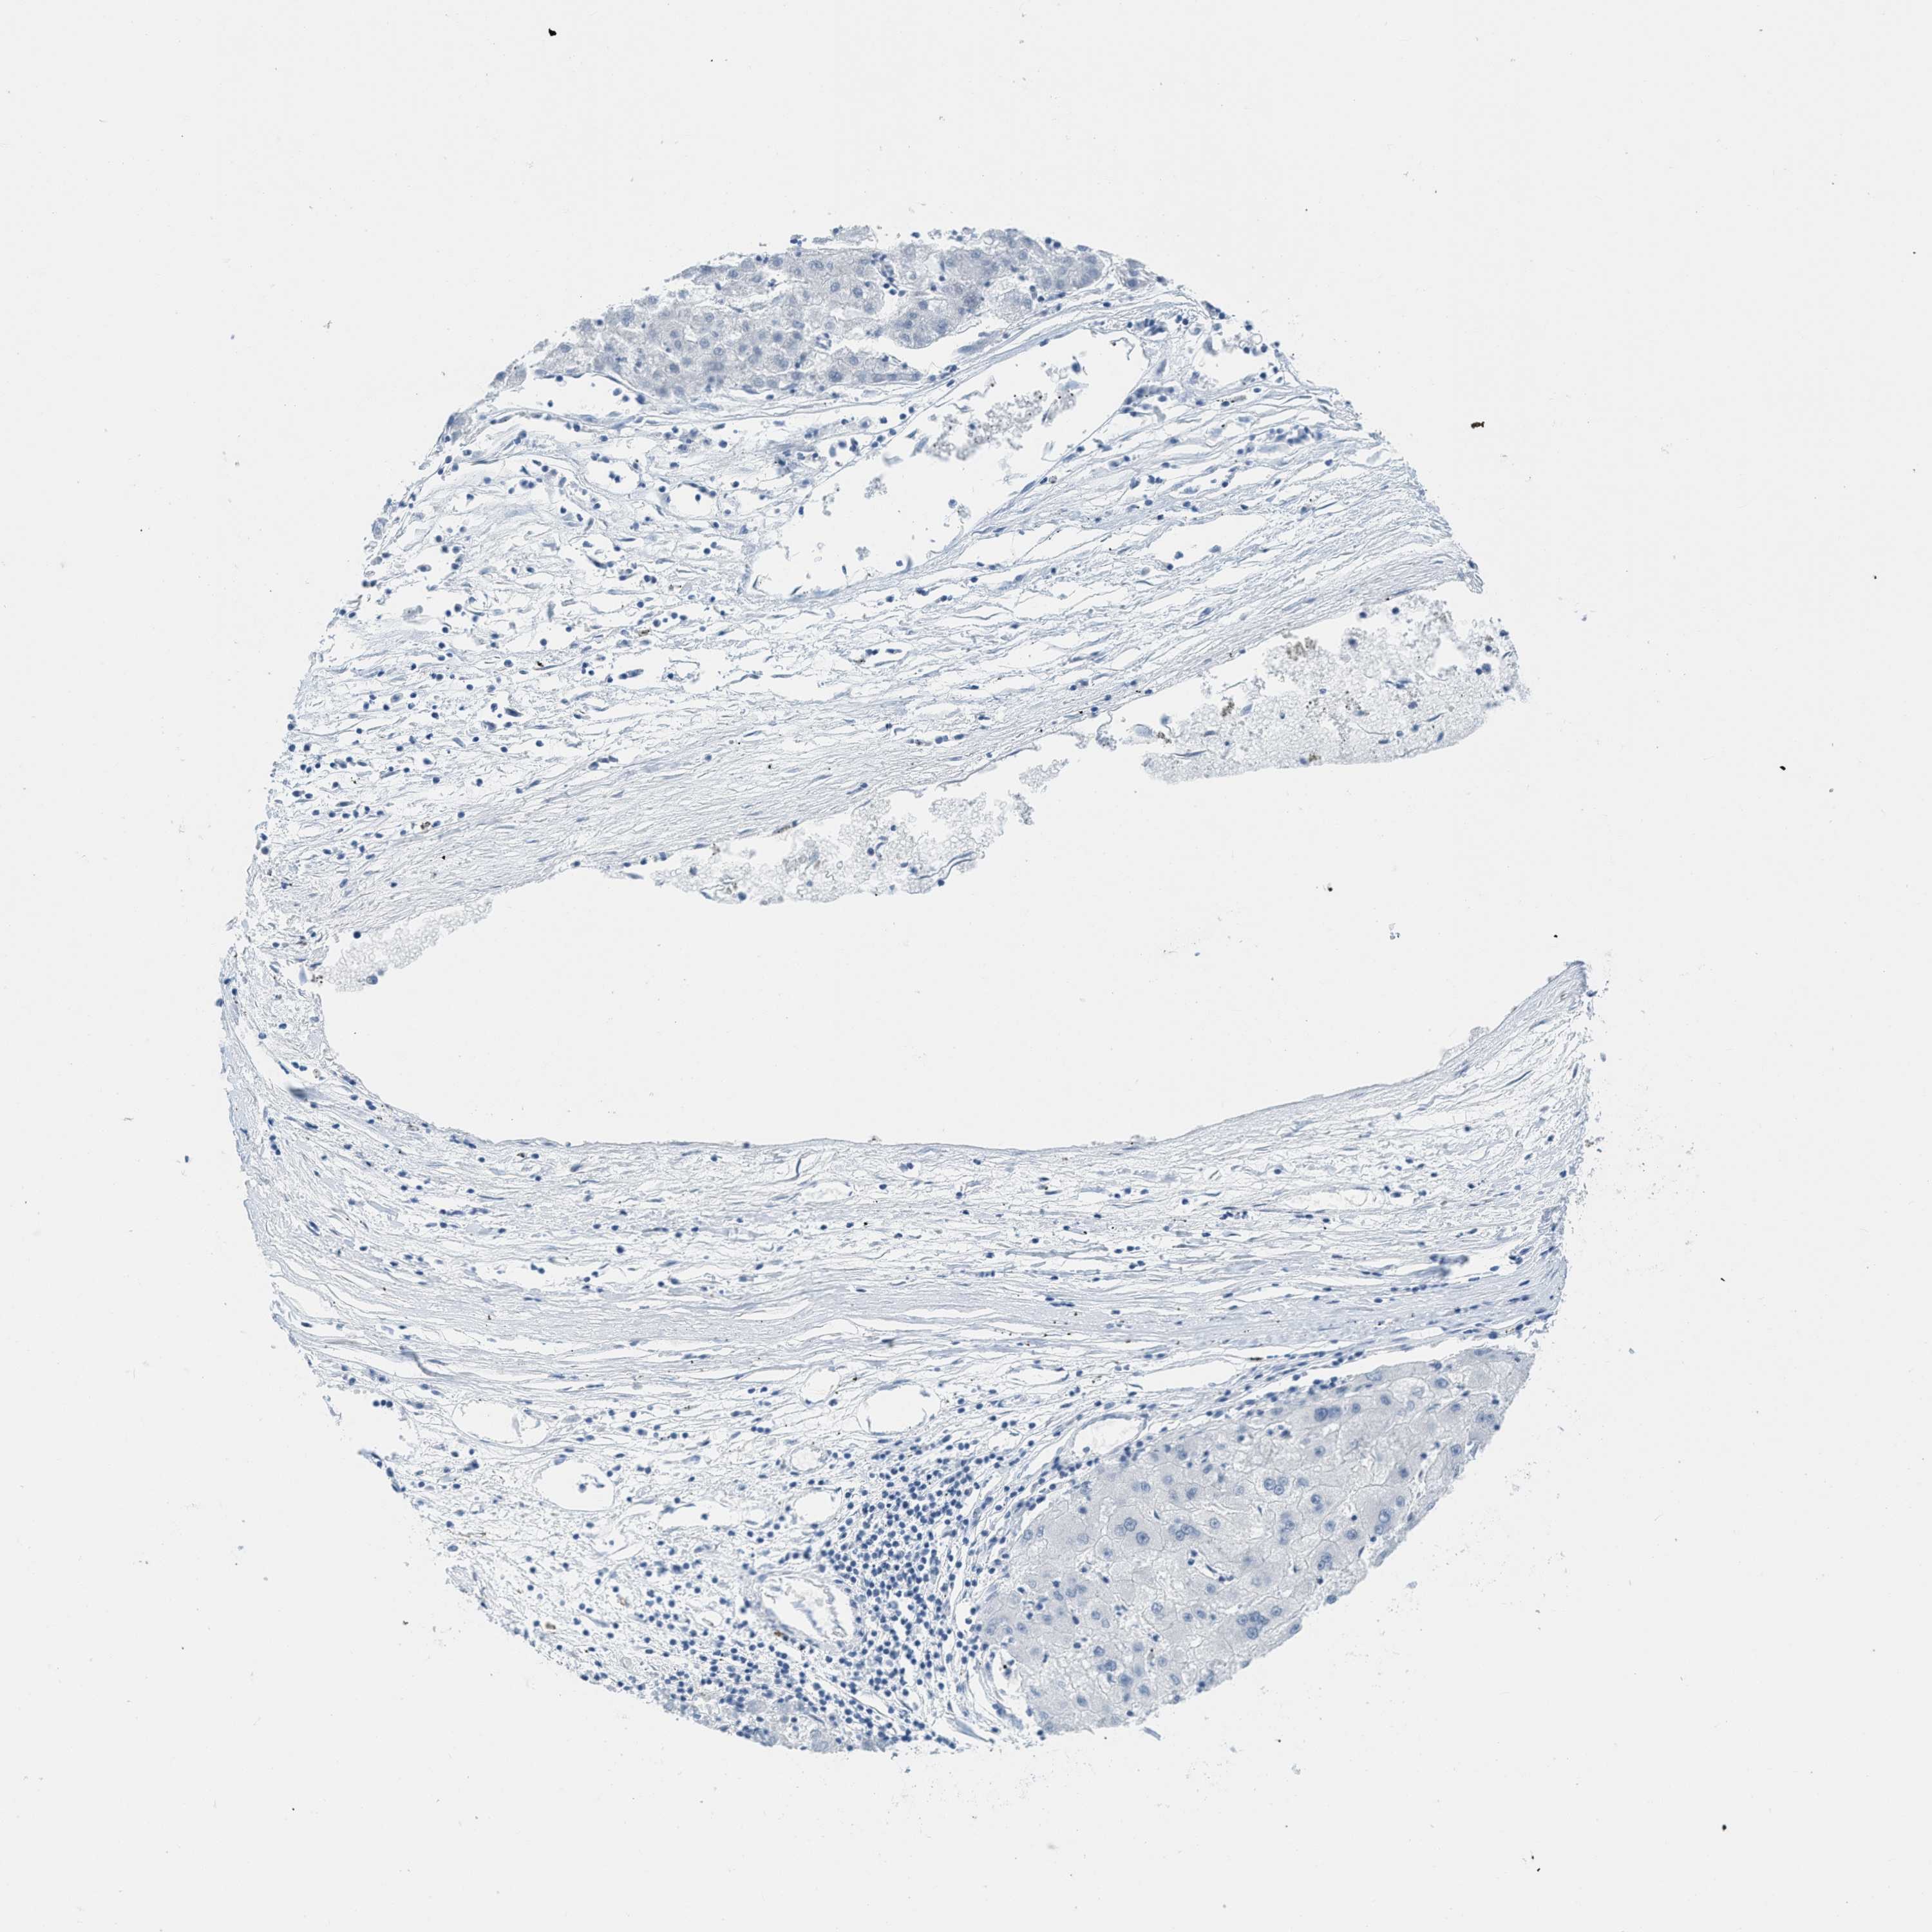

LIVER CANCER - Protein expressioni

A mouse-over function shows sample information and annotation data. Click on an image to view it in a full screen mode. Samples can be filtered based on level of antibody staining by selecting one or several of the following categories: high, medium, low and not detected. The assay and annotation is described here.

Note that samples used for immunohistochemistry by the Human Protein Atlas do not correspond to samples in the TCGA dataset.

Antibody stainingi

Antibody staining in the annotated cell types in the current human tissue is reported as not detected, low, medium, or high, based on conventional immunohistochemistry profiling in selected tissues. This score is based on the combination of the staining intensity and fraction of stained cells.

Each image is clickable and will lead to virtual microscopy that enables deeper exploration of all samples and also displays staining intensity scores, fraction scores and subcellular localization as well as patient and tissue information for each sample.

Antibody HPA003505

Antibody HPA003881

Antibody CAB018768

Staining

High

Medium

Low

Not detected

Intensity

Strong

Moderate

Weak

Negative

Quantity

>75%

75%-25%

<25%

None

Location

Nuclear

Cytoplasmic/membranous

Cytoplasmic/membranous,nuclear

Carcinoma, Hepatocellular, NOS

Cholangiocarcinoma